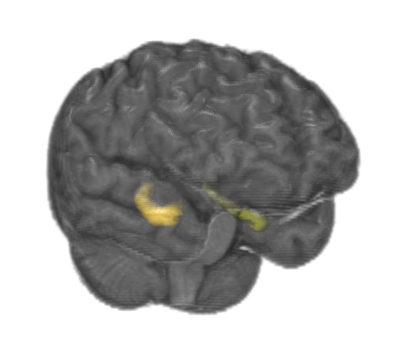

Refer to caption

Figure 3: Hippocampus

The hippocampus is a component of human brains responsible for committing short-term episodic and declarative memory into long-term memory, as well as navigation [29]. Hippocampus segmentation is important in the diagnosis of Alzheimer’s disease (AD), as it is one of the components first affected by the disease. A reduction in hippocampal volume can be used as a marker for AD diagnosis [30].

Humans have 2 hippocampi, shaped like seahorses, as shown in Figure 3. Our goal is to classify each voxel in an MR Image as non-hippocampus, left hippocampus, or right hippocampus. We are using this problem to evaluate different deep learning techniques for patch-based segmentation. All images are labeled by one human expert. Unfortunately, none of the images have been labeled by more than 1 human expert to determine variances in human labeling.